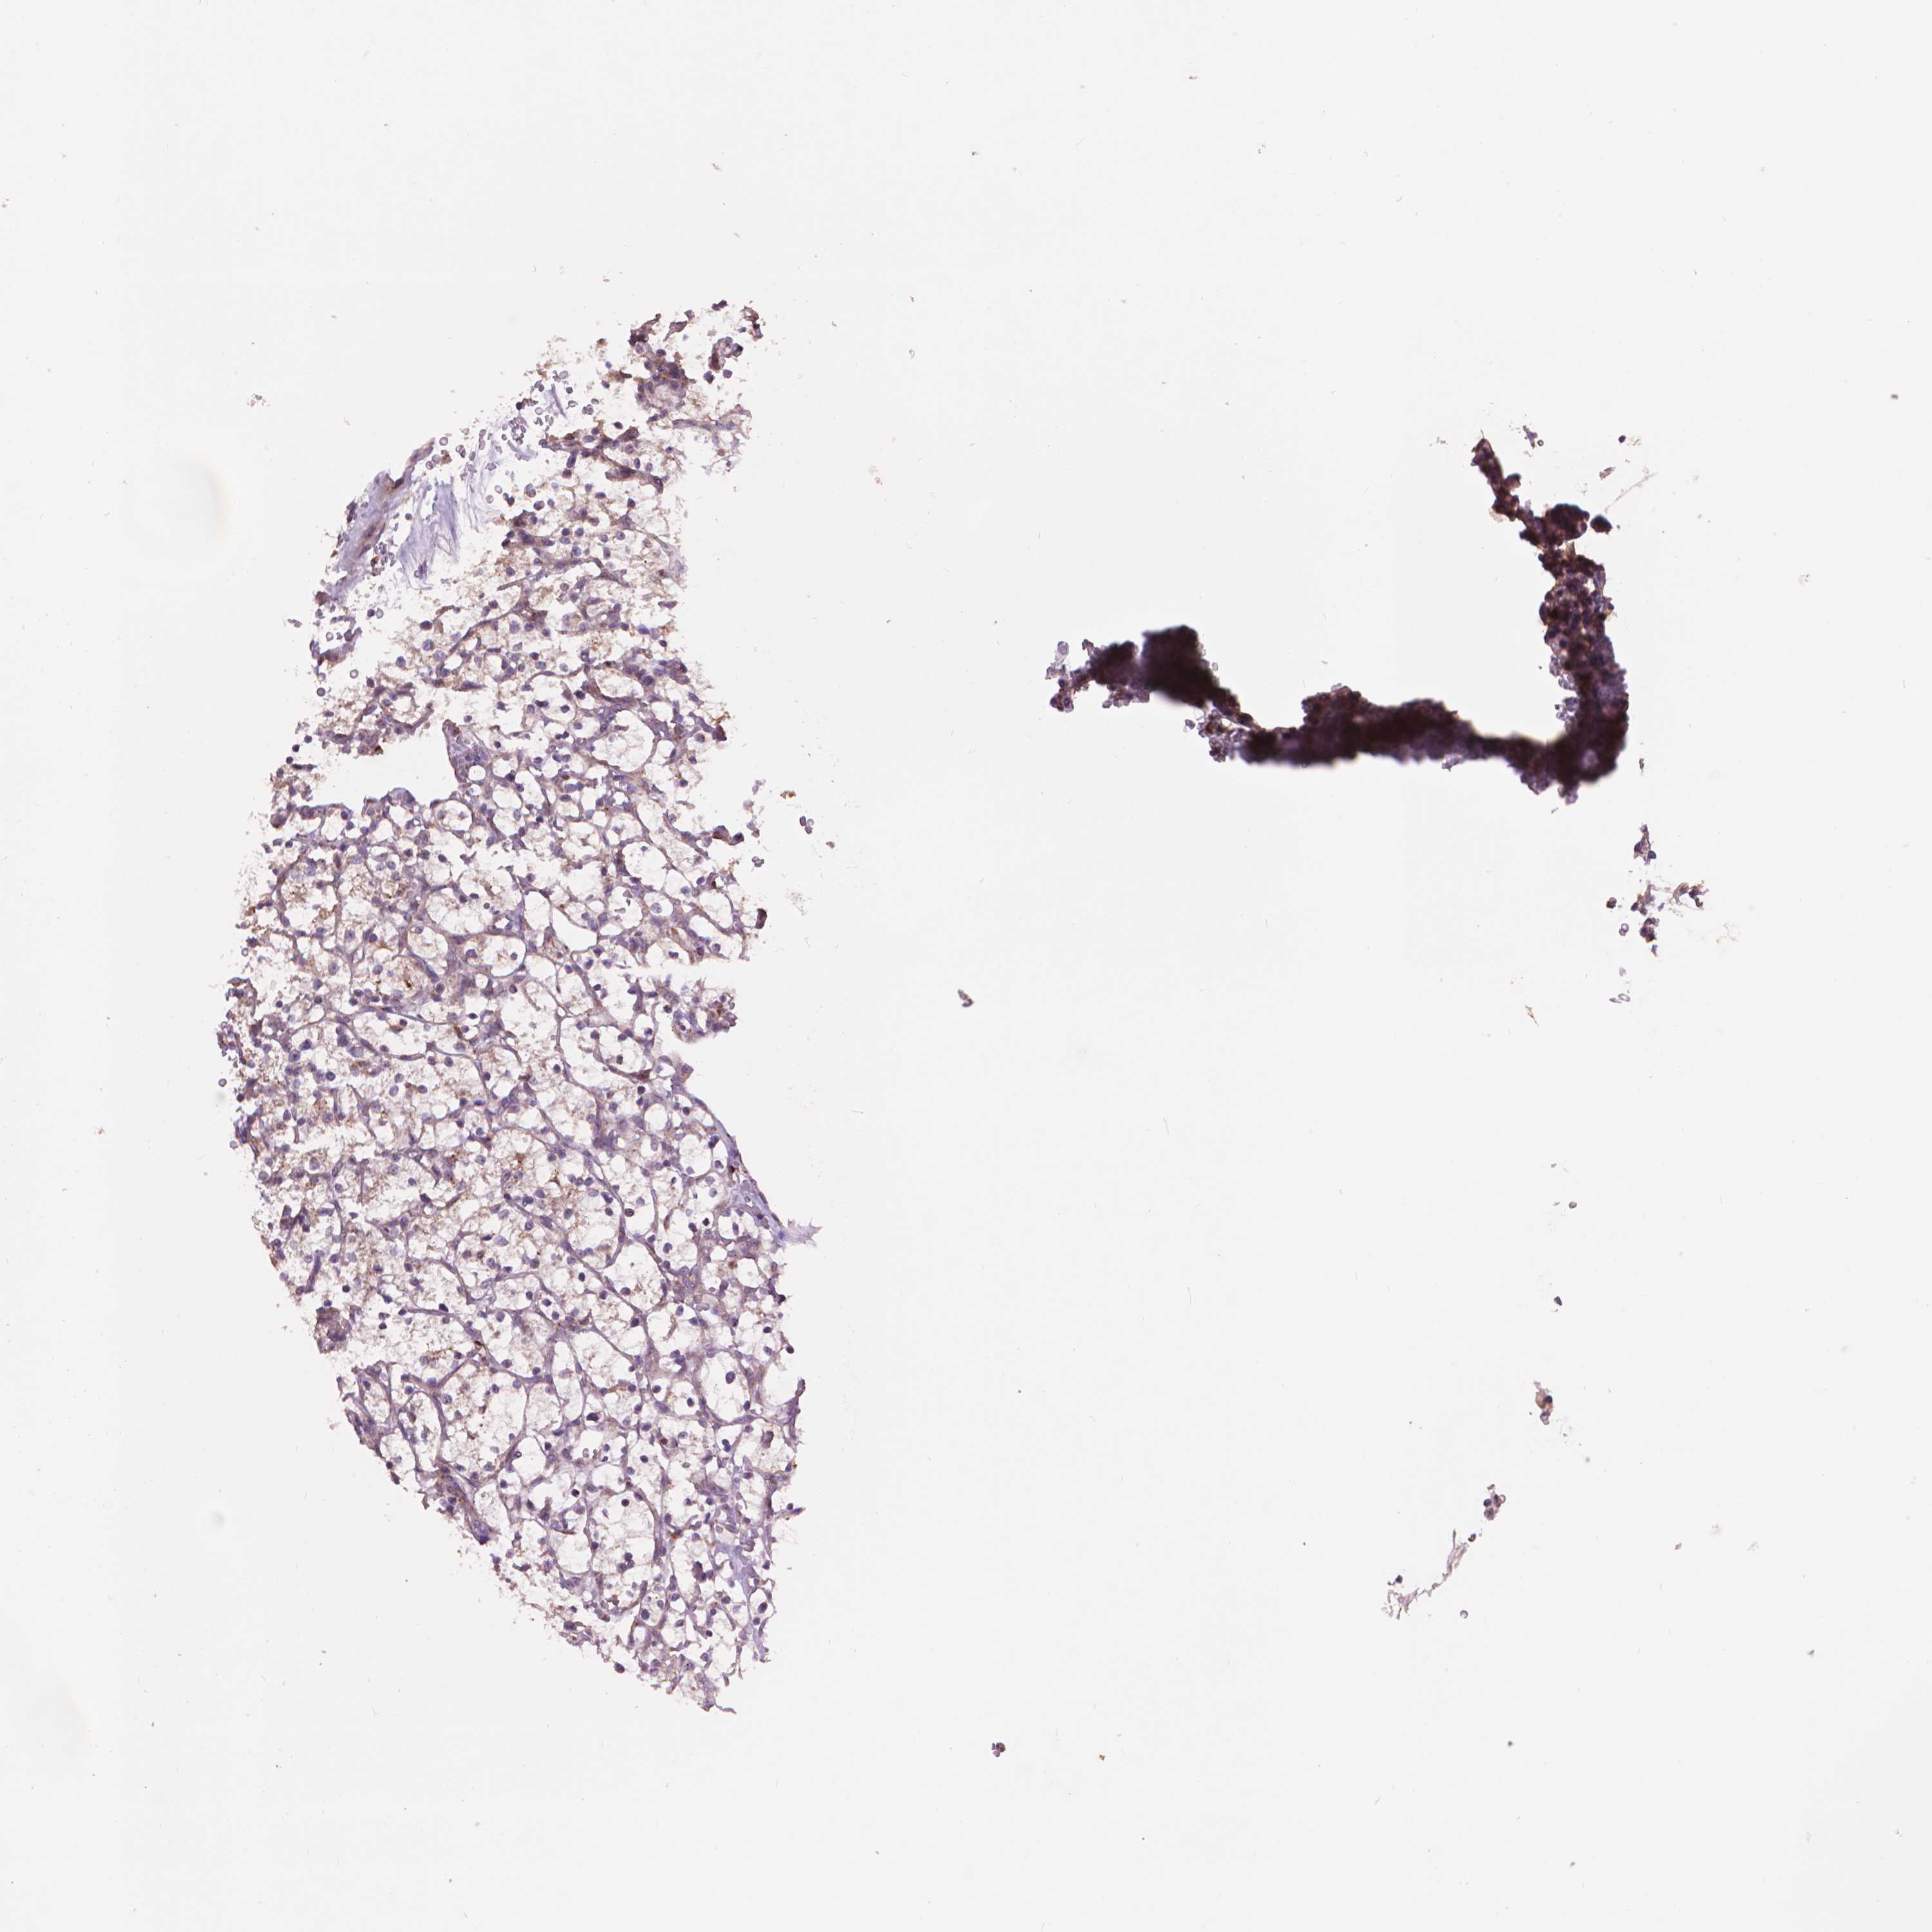

KIDNEY RENAL PAPILLARY CELL CARCINOMA (TCGA) - Interactive survival scatter ploti

The Survival Scatter plot shows the clinical status (i.e. dead or alive) for all individuals in the patient cohort, based on the same data that underlies the corresponding Kaplan-Meier plots. Patients that are alive at last time for follow-up are shown in blue and patients who have died during the study are shown in red.

The x-axis shows the expression levels (FPKM) of the investigated gene in the tumor tissue at the time of diagnosis. The y-axis shows the follow-up time after diagnosis (years). Both axes are complimented with kernel density curves demonstrating the data density over the axes. The top density plot shows the expression levels (FPKM) distribution among dead (red) and alive patients (blue). The right density plot shows the data density of the survived years of dead patients with high and low expression levels respectively, stratified using the cutoff indicated by the vertical dashed line through the Survival Scatter plot. This cutoff is automatically defined based on the FPKM cutoff that minimizes the p-score. The cutoff can be changed by dragging the vertical line or by entering a cutoff value in the square labeled "Current cut-off".

Under the Survival Scatter plot the p-score landscape (black curve; left axis) is shown together with dead median separation (red curve; right axis). Dead median separation is the difference in median mRNA expression between patients who have died with high and low expression, respectively. It is calculated as follows: median FPKM expression of dead patients with high expression - median FPKM expression of dead patients with low expression. This is intended to aid the user in visually exploring custom cutoffs and the associated p-scores and dead median separation.

Individual patient data is displayed and can be filtered by clicking on one or more of the category buttons on the top of the page. Categories describing expression level and patient information include: high, low, alive, dead, female, male and tumor stages. The scale of the x-axis can be toggled between linear and log-scale by clicking on the "x log" button. Mouse-over function shows TCGA ID, patient information and mRNA expression (FPKM) for each patient.

& Survival analysisi

Kaplan-Meier plots summarize results from analysis of correlation between mRNA expression level and patient survival. Patients were divided based on level of expression into one of the two groups "low" (under cut off) or "high" (over cut off). X-axis shows time for survival (years) and y-axis shows the probability of survival, where 1.0 corresponds to 100 percent.

GLB1 is not prognostic in Kidney Renal Papillary Cell Carcinoma (TCGA)